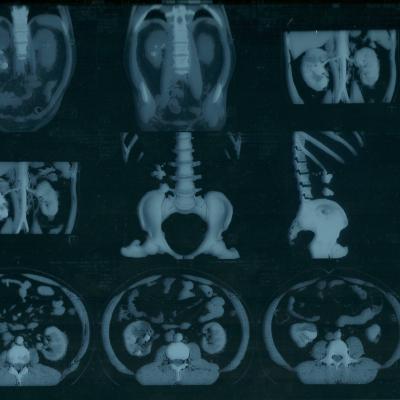

коралловидный камень

Морозов Алексей. Здравствуйте,находился

на лечении в урологическом отделении

г.Йошкар-Ола по поводу МКБ, В правой почке

обнаружен коралловидный камень,врач

рекомендовал ЧПНЛ в Нижнем Новгороде,но